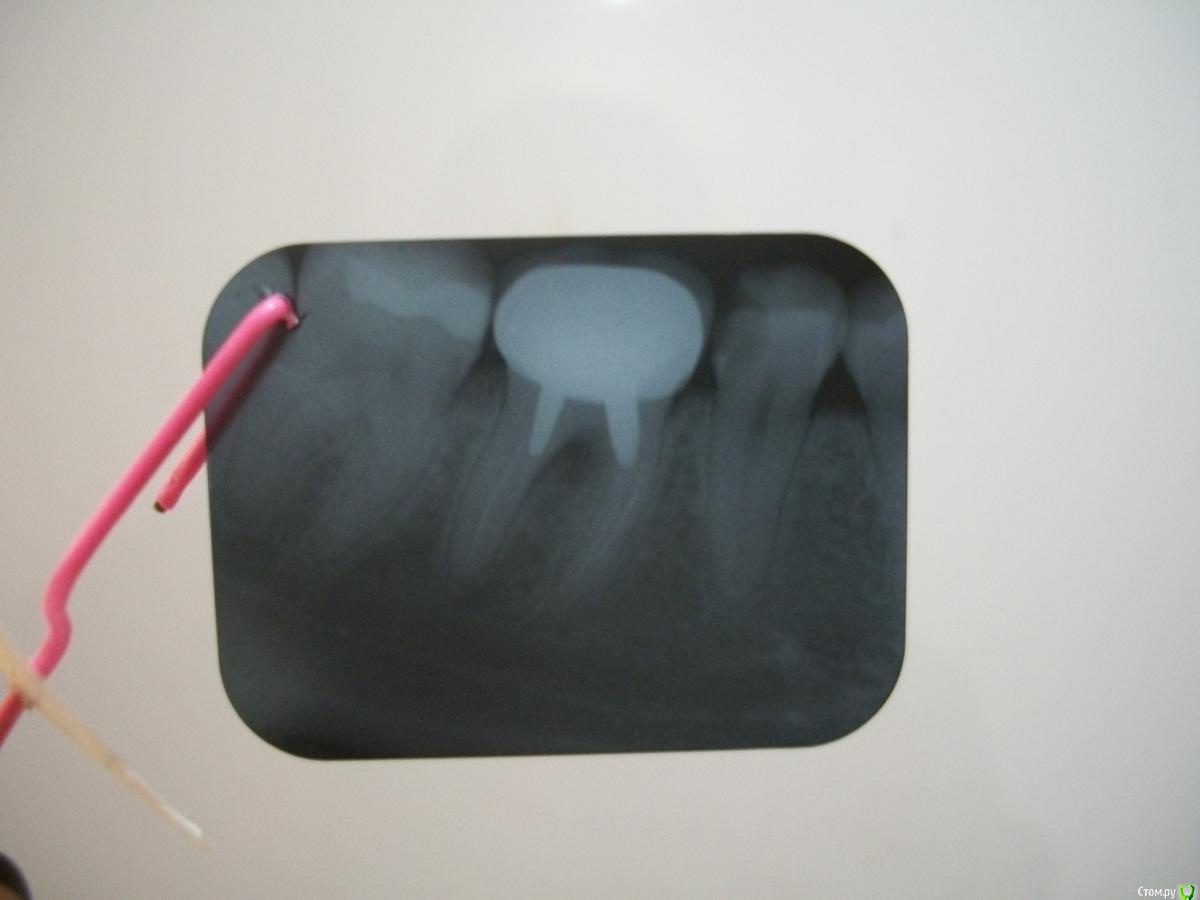

анет Опубликовано 28 апреля, 2016 Поделиться Опубликовано 28 апреля, 2016 Добрый день форумчане. Помогите пожалуйста решить наболевший вопрос. Месяц назад у меня разболелся 6 нижний зуб, а точнее то, что от него осталось (осталась только одна часть стенки зуба). Решила я поставить металлокерамическую коронку. Врач стоматолог почистил каналы, поставил металлическую вкладку и одел коронку, но ВСЕ ЭТО БЕЗ РЕНТГЕНА. На протяжении месяца боль при накусывании на зуб не утихала и он мне его сточил, но безрезультатно. В другой больнице я сделала рентген и оказалось, что там межкорневое воспаление и зуб нужно только удалять. Вопрос: зачем мне ставили коронку, чтобы потом удалить ее вместе с зубом??? Есть ли шанс вернуть деньги за некачественно оказанную услугу? Рентген прилагается Ссылка на комментарий